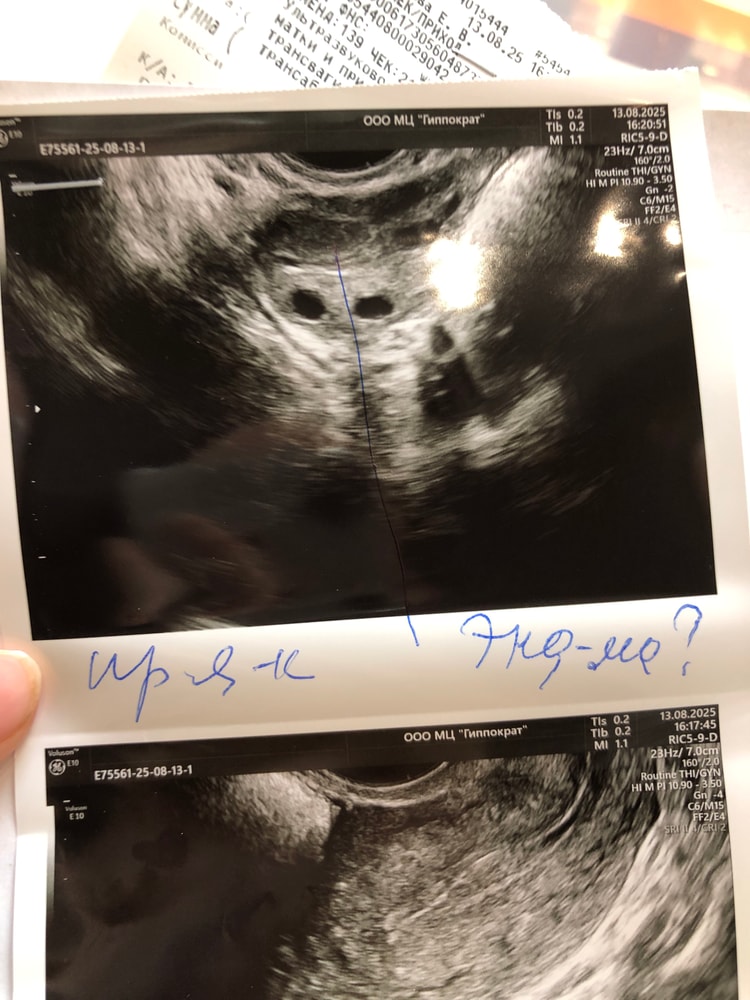

Я уже не знаю что делать с этим эндометрием😭

Что скажете? Была операция 2 месяца назад, ужи опять говорит что подозрение на гиперплазию, и что за эндометриома, никогда не было его у меня, по гистологии пришло что гиперплазии нет, в общем я с ума сойду скоро, а ляльку так и хочется(((

По фото с эндометрий действительно что-то не так. Я бы сделала рдв и растила новый свежий